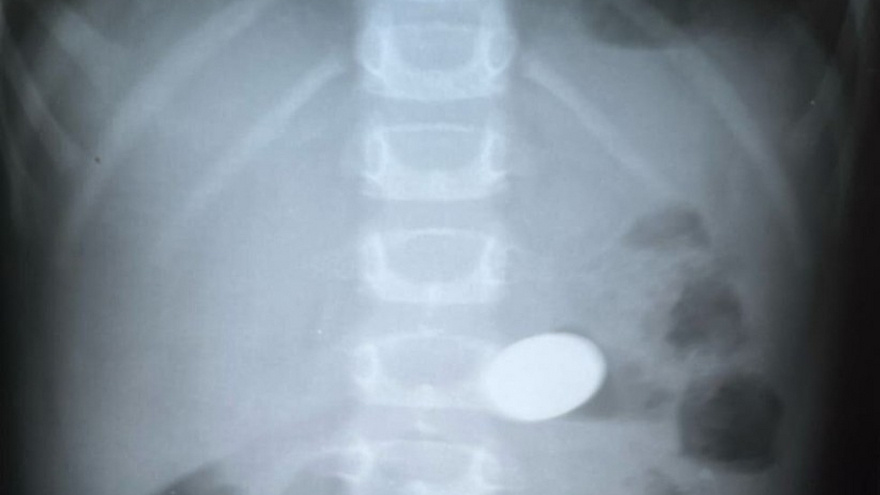

Кроме того, по словам балаковских медиков, к ним часто поступают дети, которые "упорно считают себя сейфами". Одним из таких пациентов оказался 5-летний ребенок. Врачи с помощью эндоскопа достали из него через рот 10-рублевую монету.

В больницу также поступили 10-месячные двойняшки, мама которых заподозрила, что они проглотили детали конструктора. На рентгене врачи ничего не нашли, в итоге детей отпустили домой. Родителям велели снова привезти детей на осмотр, если будут тревожные сигналы.